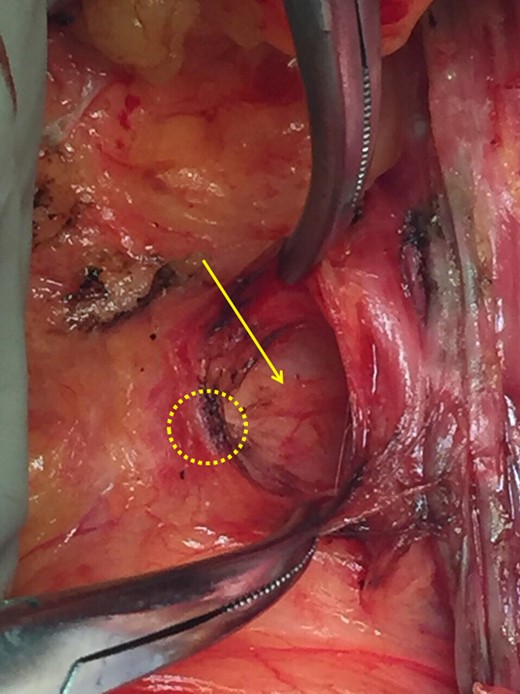

Yellow circle: the malignant tumor, black arrow: clavipectoral fascia, yellow arrow: incision of the clavipectoral fascia reveals if the mass is lymphatic or part of the axillary tail of Spence.